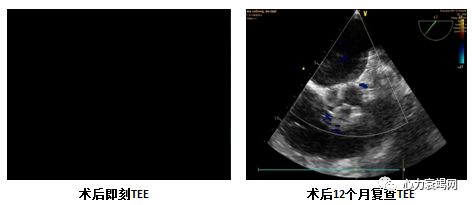

术后即刻微量残余分流,直径1mm,提示成功

术后3月及12月复查TEE提示植入成功,未见残余分流

随访24个月,无严重不良事件发生